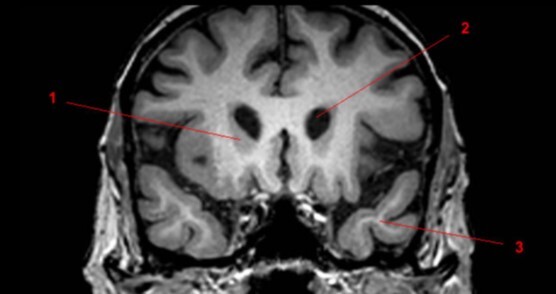

Label 1-3

A

1. Rt caudate nucleus

2. Lt lateral ventricle

3. Lt temporal lobe